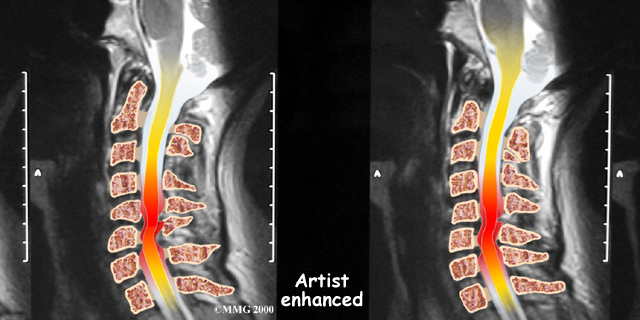

If more information is needed, your doctor may order a magnetic resonance imaging (MRI) scan. The MRI machine uses magnetic waves rather than X-rays to show the soft tissues of the body. This test gives a clear picture of the spinal cord and can show where it is being squeezed. This machine creates pictures that look like slices of the area your doctor is interested in. The test does not require any special dye or a needle.